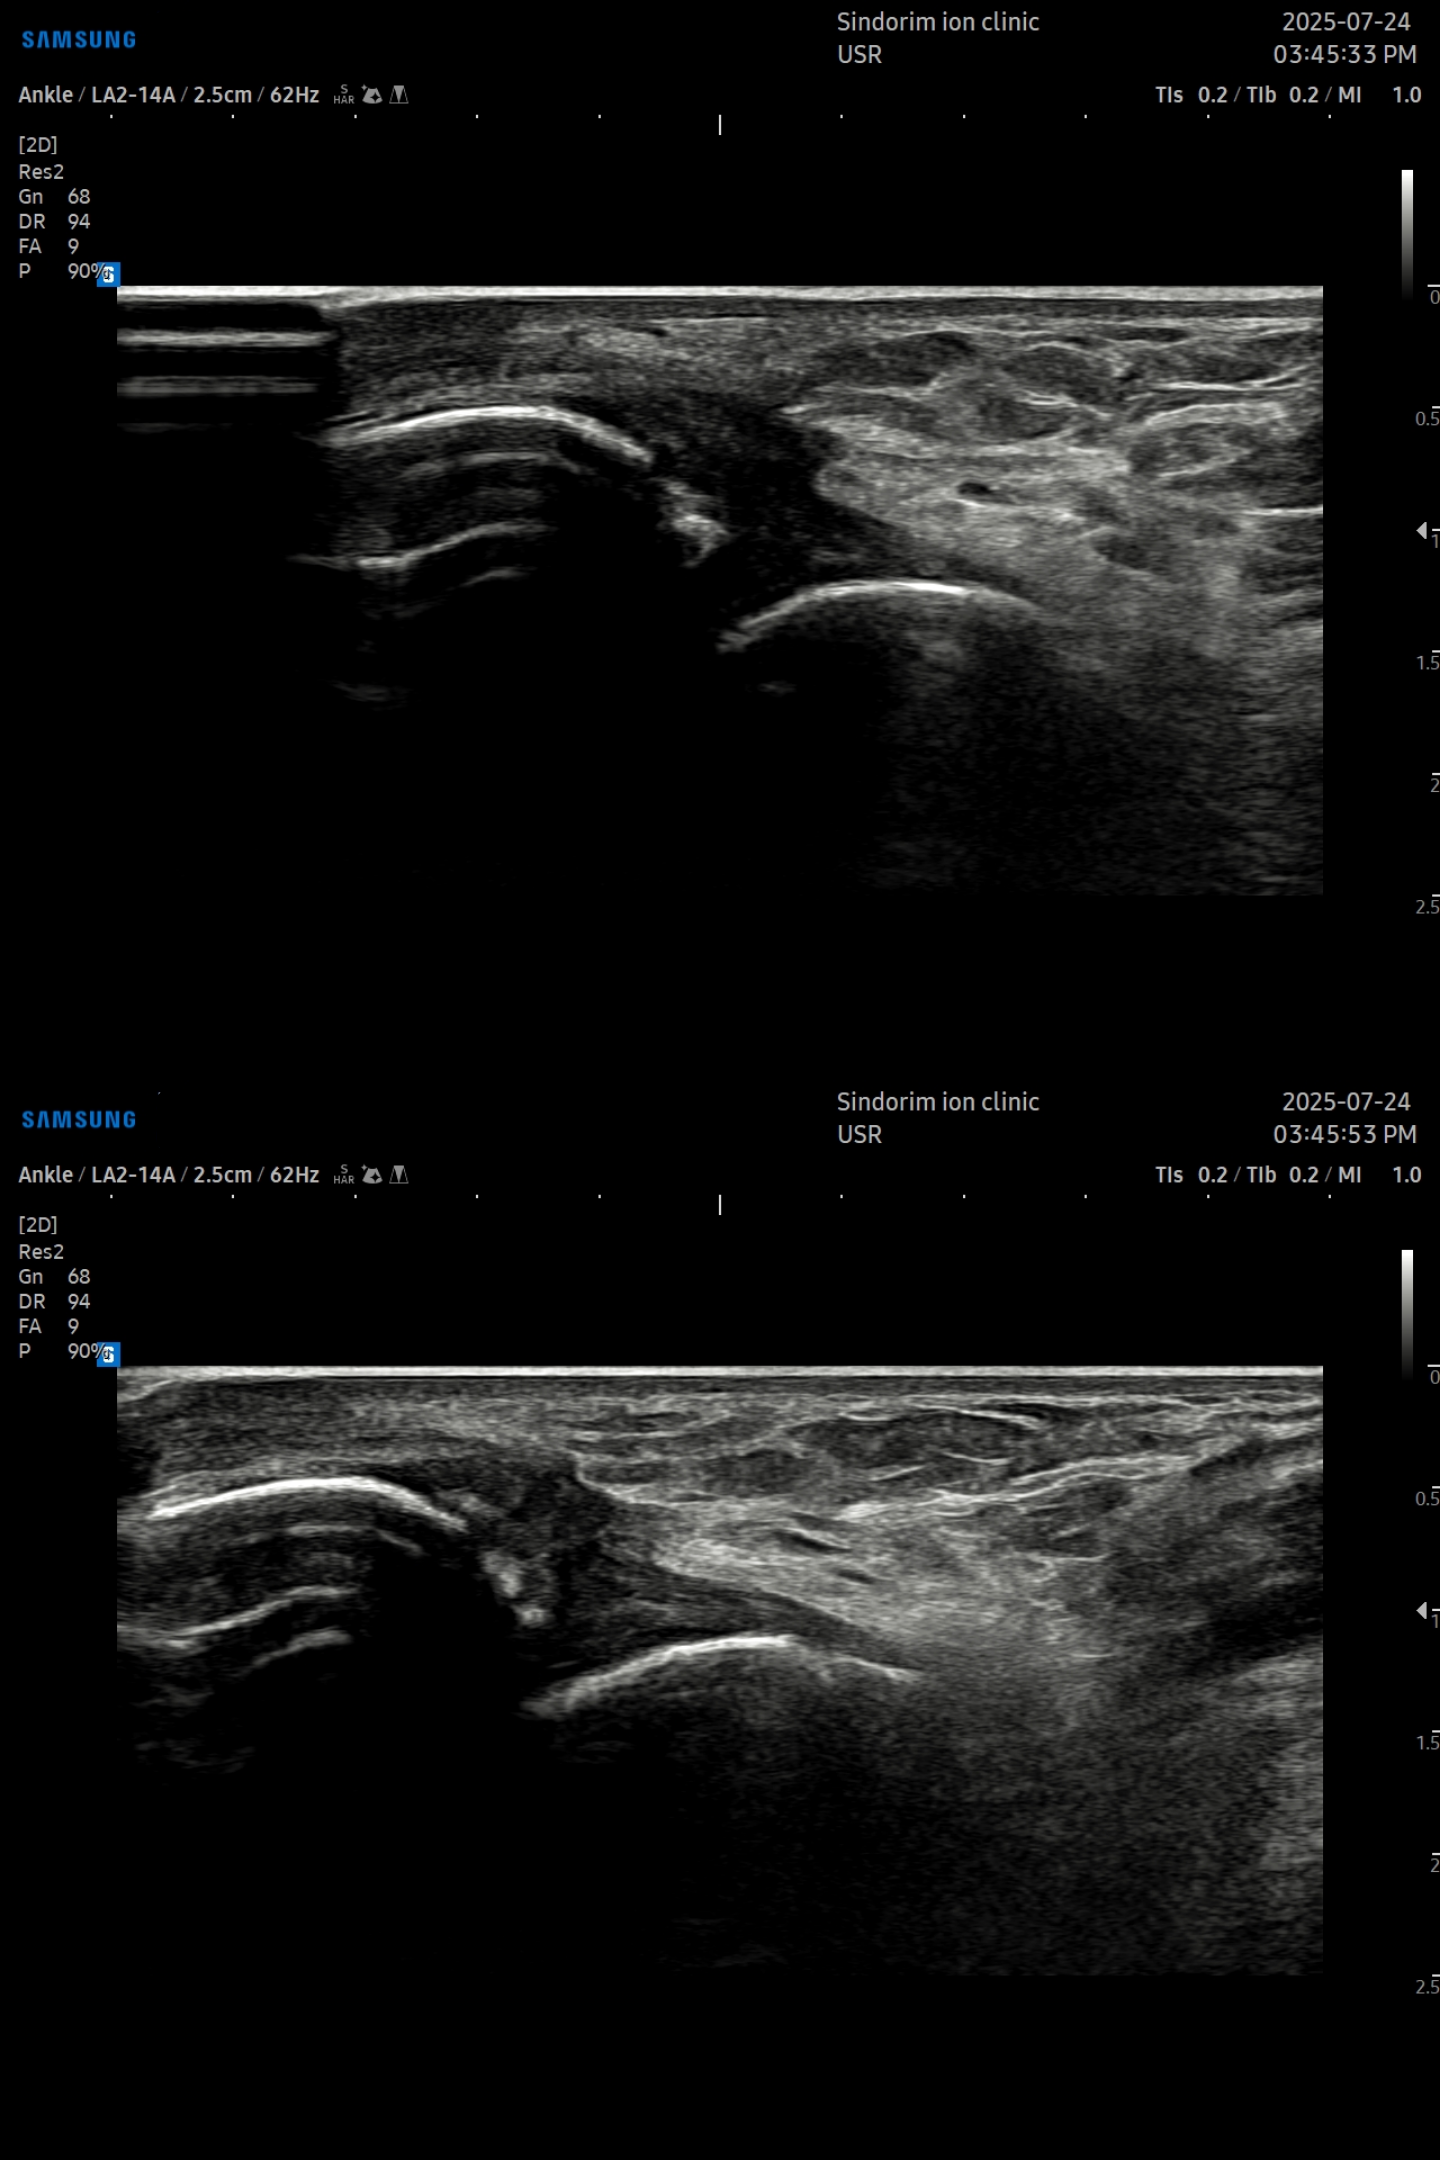

- 치료기간 : 25 .7 . 24 ~ 25 . 9 . 19

- 치료횟수 : 20 회

치료 전

치료 후